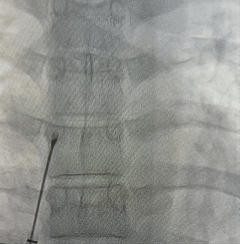

DSA下左盘展开

左盘面贴靠房间隔

右盘展开

固定钢缆,后撤鞘管展开右盘

DSA下牵拉试验

验证封堵器稳定夹持于缺损处

DSA下逆时针旋转解脱钢缆,释放封堵器